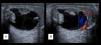

Los niveles de α-fetoproteína (AFP) estaban elevados en 5 de los pacientes (aquellos que presentaron tumor de saco vitelino o carcinoma embrionario). Se realizó una ecografía testicular en 11 de los 15 pacientes, confirmándose la presencia de una masa en 9 de los casos (figs. 1 y 2). Se hizo una estudio de extensión mediante pruebas de imagen (radiografía de tórax, escáner toracoabdominal, resonancia magnética (RM) y/o gammagrafía ósea) en 10 pacientes (fig. 3).

La ecografía tiene casi un 100% de sensibilidad para detectar neoplasias testiculares. El eco-Doppler puede ser de utilidad para el diagnóstico, valorando un posible aumento del flujo vascular1. Los tumores benignos aparecerán como masas bien definidas, de bordes delimitados y escasa vascularización. Los quistes epidermoides aparecen como lesiones intratesticulares bien delimitadas, con un área central hipoecogénica rodeada de un halo hiperecogénico. Los tumores del saco vitelino tienen una apariencia más sólida, hipoecoica y homogénea1,18.